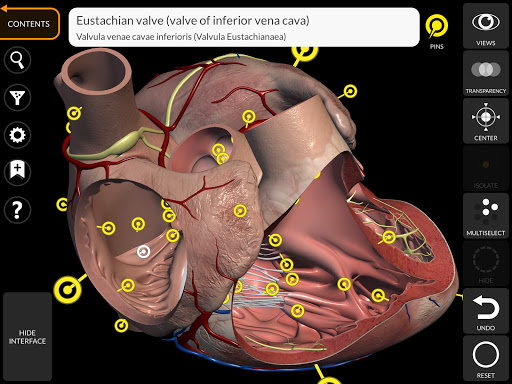

"Anatomy 3D Atlas" memungkinkan Anda mempelajari anatomi manusia dengan cara yang mudah dan interaktif.

Melalui antarmuka yang sederhana dan intuitif, Anda dapat mengamati setiap struktur anatomi dari sudut mana pun.

Model 3D anatomi sangat terperinci dan memiliki tekstur hingga resolusi 4k.

Pembagian berdasarkan wilayah dan tampilan yang telah ditetapkan sebelumnya memudahkan pengamatan dan studi bagian tunggal atau kelompok sistem dan hubungan antara organ yang berbeda.

MODEL ANATOMI 3D

• Sistem kardiovaskular • Sistem

saraf • Sistem pernapasan • Sistem pencernaan • Sistem urogenital (pria dan wanita) • Sistem endokrin • Sistem limfatik • Sistem mata dan telinga FITUR • Antarmuka yang sederhana dan intuitif • Putar dan perbesar setiap model dalam ruang 3D • Opsi untuk menyembunyikan atau mengisolasi satu atau beberapa model yang dipilih • Filter untuk menyembunyikan atau menampilkan setiap sistem • Fungsi pencarian untuk menemukan setiap bagian anatomi dengan mudah • Fungsi penanda untuk menyimpan tampilan khusus • Rotasi cerdas yang menggerakkan pusat rotasi secara otomatis • Fungsi transparansi • Visualisasi otot melalui tingkat lapisan dari yang superfisial hingga yang terdalam • Dengan memilih model atau pin, istilah anatomi terkait akan muncul • Deskripsi otot: asal, • Tampilkan/ Sembunyikan antarmuka UI (sangat berguna dengan layar kecil) MULTIBAHASA • Istilah anatomi dan antarmuka pengguna tersedia dalam 11 bahasa: Latin, Inggris, Prancis, Jerman, Italia, Portugis, Turki, Rusia, Spanyol, Mandarin, Jepang, dan Korea • Istilah anatomi dapat ditampilkan dalam dua bahasa secara bersamaan PERSYARATAN SISTEM • Android 8.0 atau yang lebih baru, perangkat dengan RAM minimal 3GB Reversi